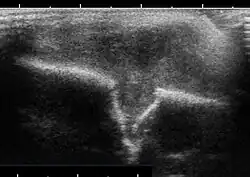

Im Ultraschall lässt sich die Weichteilkomponente sowie die knöcherne Destruktion gut nachweisen, charakteristisch ist an der Kalotte die gestufte unterschiedliche Destruktion im Knochen (Tabula externa).